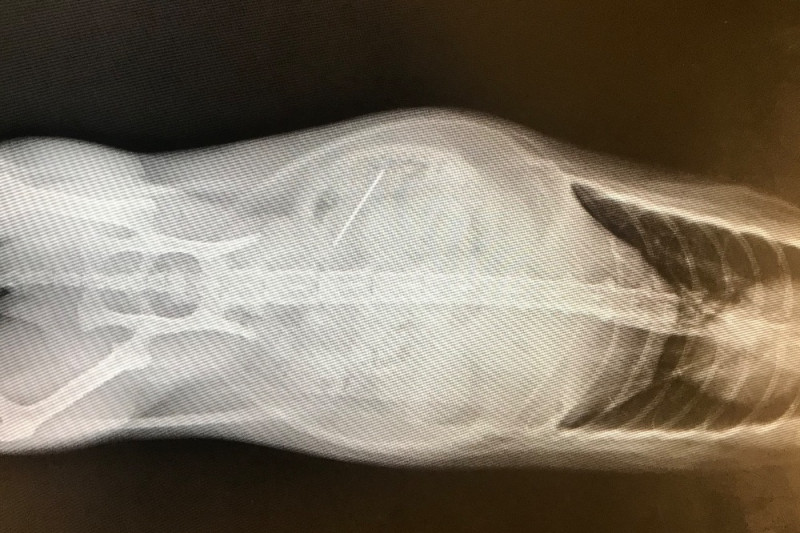

Our dear sweet Ratt in her infinite quest to eat everything has swallowed a sewing needle which became lodged in her small intestine. The needle is causing her infections and punctures and needs to be extracted by emergency surgery.